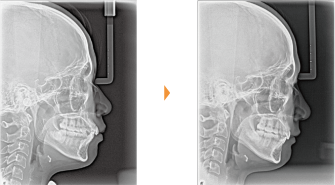

| 主訴 | 前歯が出ている |

| 年齢・性別 | 35歳 / 女性 |

| 治療方針 | 叢生も前歯の突出も大きいケース。小臼歯抜歯だけでは改善できないため、大臼歯の抜歯も行なった。 |

| 抜歯部位 | 上下顎左右小臼歯、左上第1大臼歯(計5本) |

| 使用装置 | マルチブラケット装置 |

| 治療期間 | 36か月 |

| リテーナー | 上顎インビジブル、フィックス、下顎インビジブル |

| 費用 | 885,000円(税別) |